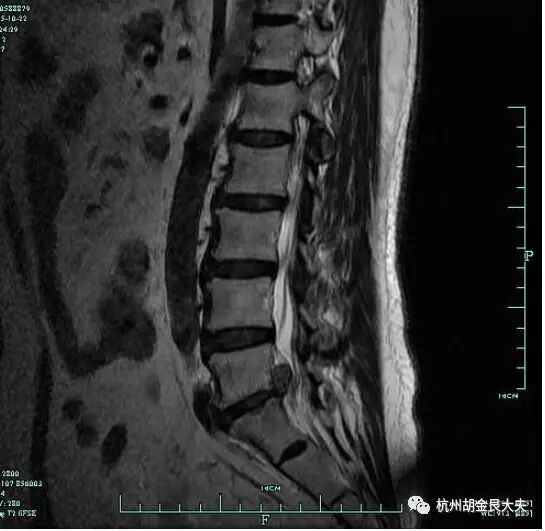

试题:患者腰痛2年,加重3天,摄片如下:

请给出诊断:

阅片题:

参考答案

项目 | 评分标准(请酌情打√) | √ | 分值 |

读片 | 腰5骶1 | 2 | |

腰椎间盘突出 | 8 | ||

总分 10 | |||